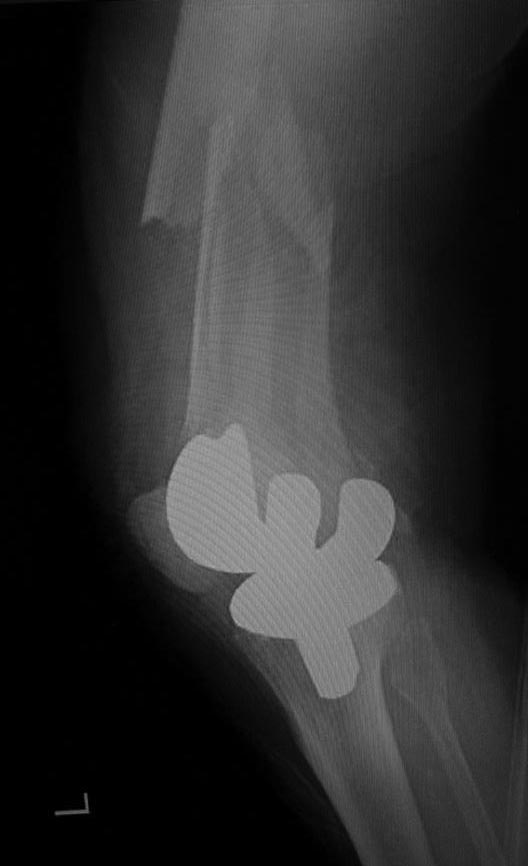

Перипротезный перелом дистального отдела бедра

Что можно сделать? Бедренный комплект бесцементный